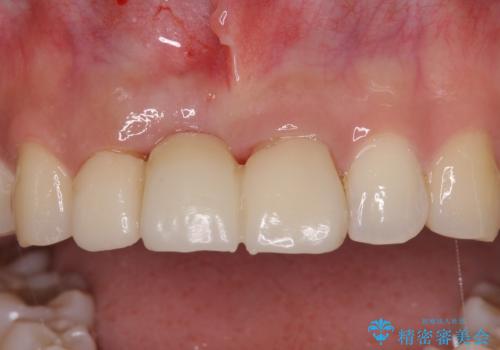

抜歯後は歯肉が痩せてしまうため、歯肉移植を行って歯肉の形態を改善した後、オールセラミックブリッジにて補綴することとしました。

歯肉移植により歯肉ラインや歯の形態を整えることができ、ブリッジによる補綴としたことで舞えば全体の色調を整えることができました。